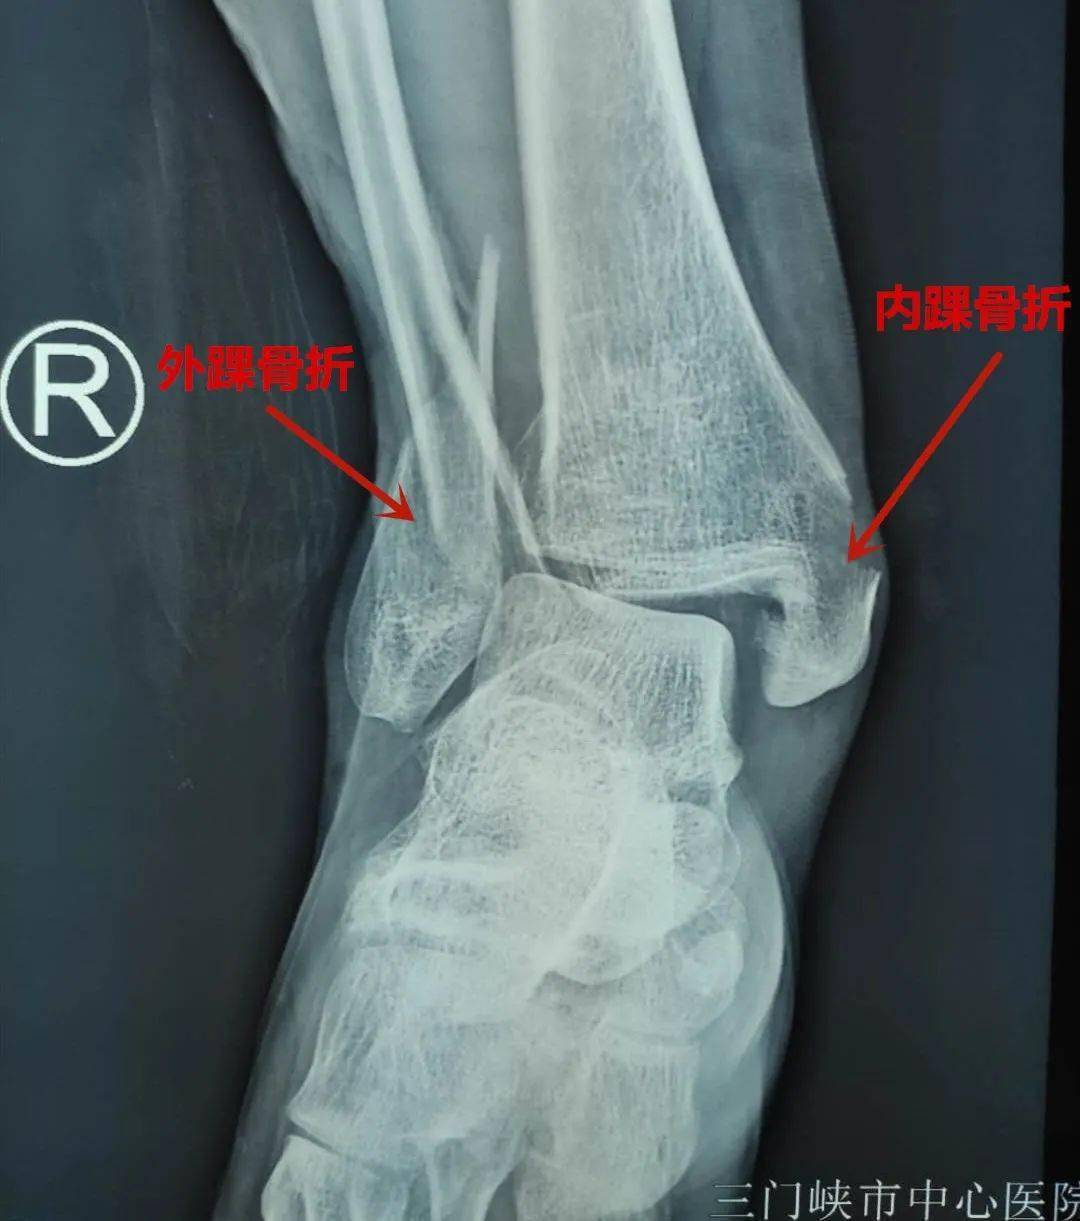

三踝骨折

三踝骨折常规手术

三踝骨折一例讨论分型及治疗